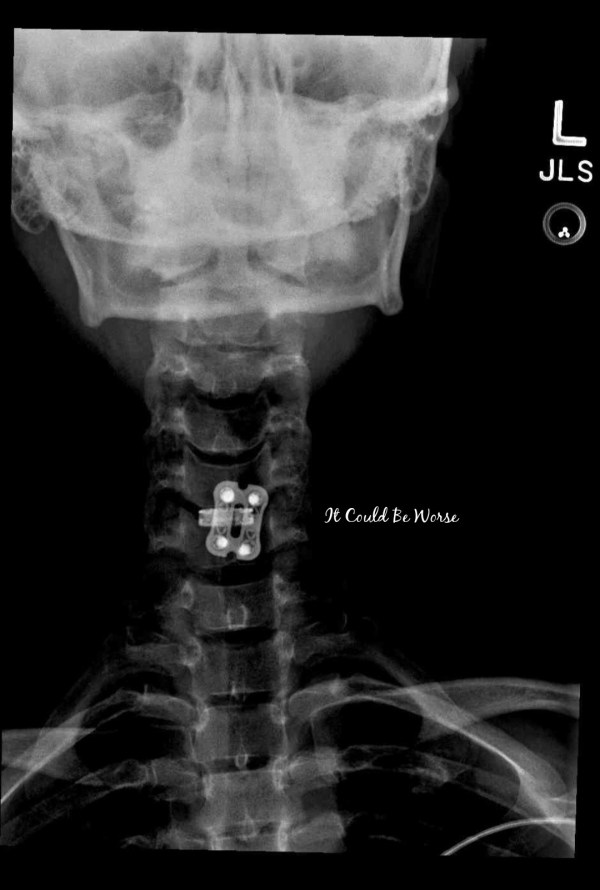

ACDF Surgery – 3 Weeks Post-Op & X-rays

Hooray for finally getting to see my new hardware! I was a little bummed last week when I didn't have X-rays taken for my two-week post-op appointment. I wanted to see where the titanium was placed and what it looked like but they told me I would have to wait and get a set done... Continue Reading →